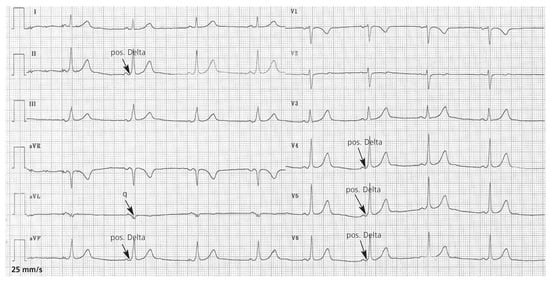

Die elektrophysiologische Untersuchung weist eine linkslaterale akzessorische Bahn nach. Nach Radiofrequenz-Katheterablation verschwinden die Delta-Wellen im Ruhe-EKG (Figure 3).

Figure 3.

Das 12-Kanal-EKG nach Radiofrequenz-Katheterablation zeigt einen normofrequenten Sinusrhythmus. Die Delta-Wellen sind verschwunden.